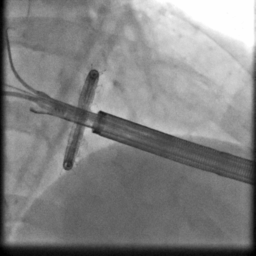

手术过程造影

手术在厦心杂交手术室进行,患者处于全麻状态,在实时三维食道超声的指引下,心外科在患者左胸前切开4-5cm的切口,经心尖预缝荷包区域导入AMEND成形环植入系统,顺利通过二尖瓣结构中央区域进入左心房后,在体外操作AMEND系统将“D”型成型环在主动脉瓣与二尖瓣间极为狭小的空间内精确释放,并先后铆钉二尖瓣环的后叶及前叶,从而达到缩小二尖瓣环的目的(图2),这一步操作要求非常精准,稍有不慎便会损伤周围组织,引起并发症。术后即刻,患者二尖瓣反流明显减轻,达到轻度水平(图3),手术从麻醉到结束平均历时3个小时。